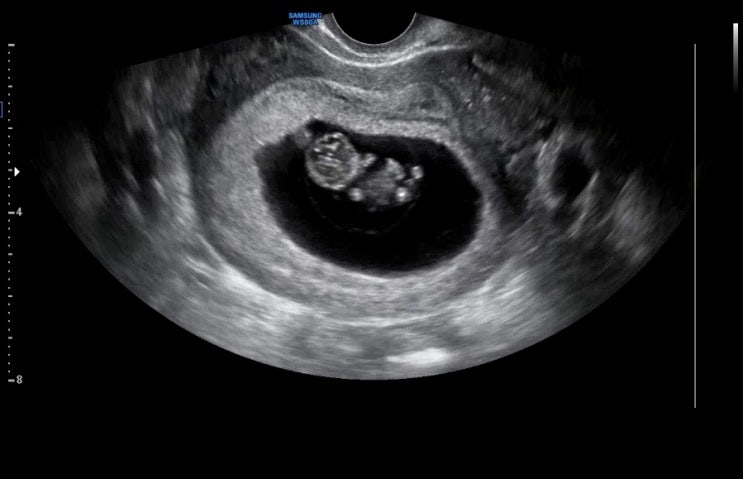

임신 8주부터의 기록! 산딸기만해진 도동이. ㅋㅋ 매 주 베이비빌리 보는 재미~ 임신하고 골프를 못치니까....